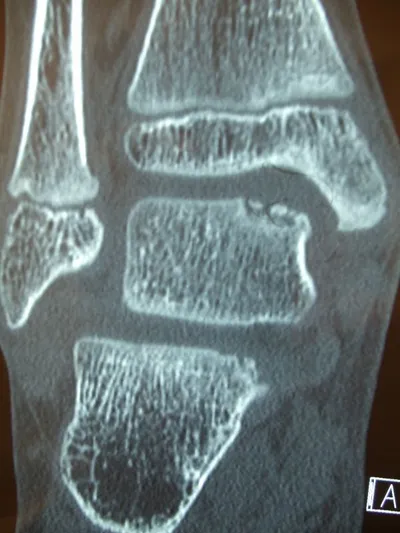

Series of Pics of Microfracture of large OCD of the Talar Dome

Pic of OCD after preparation and debridement .

Measuring the size and depth of the OCD.